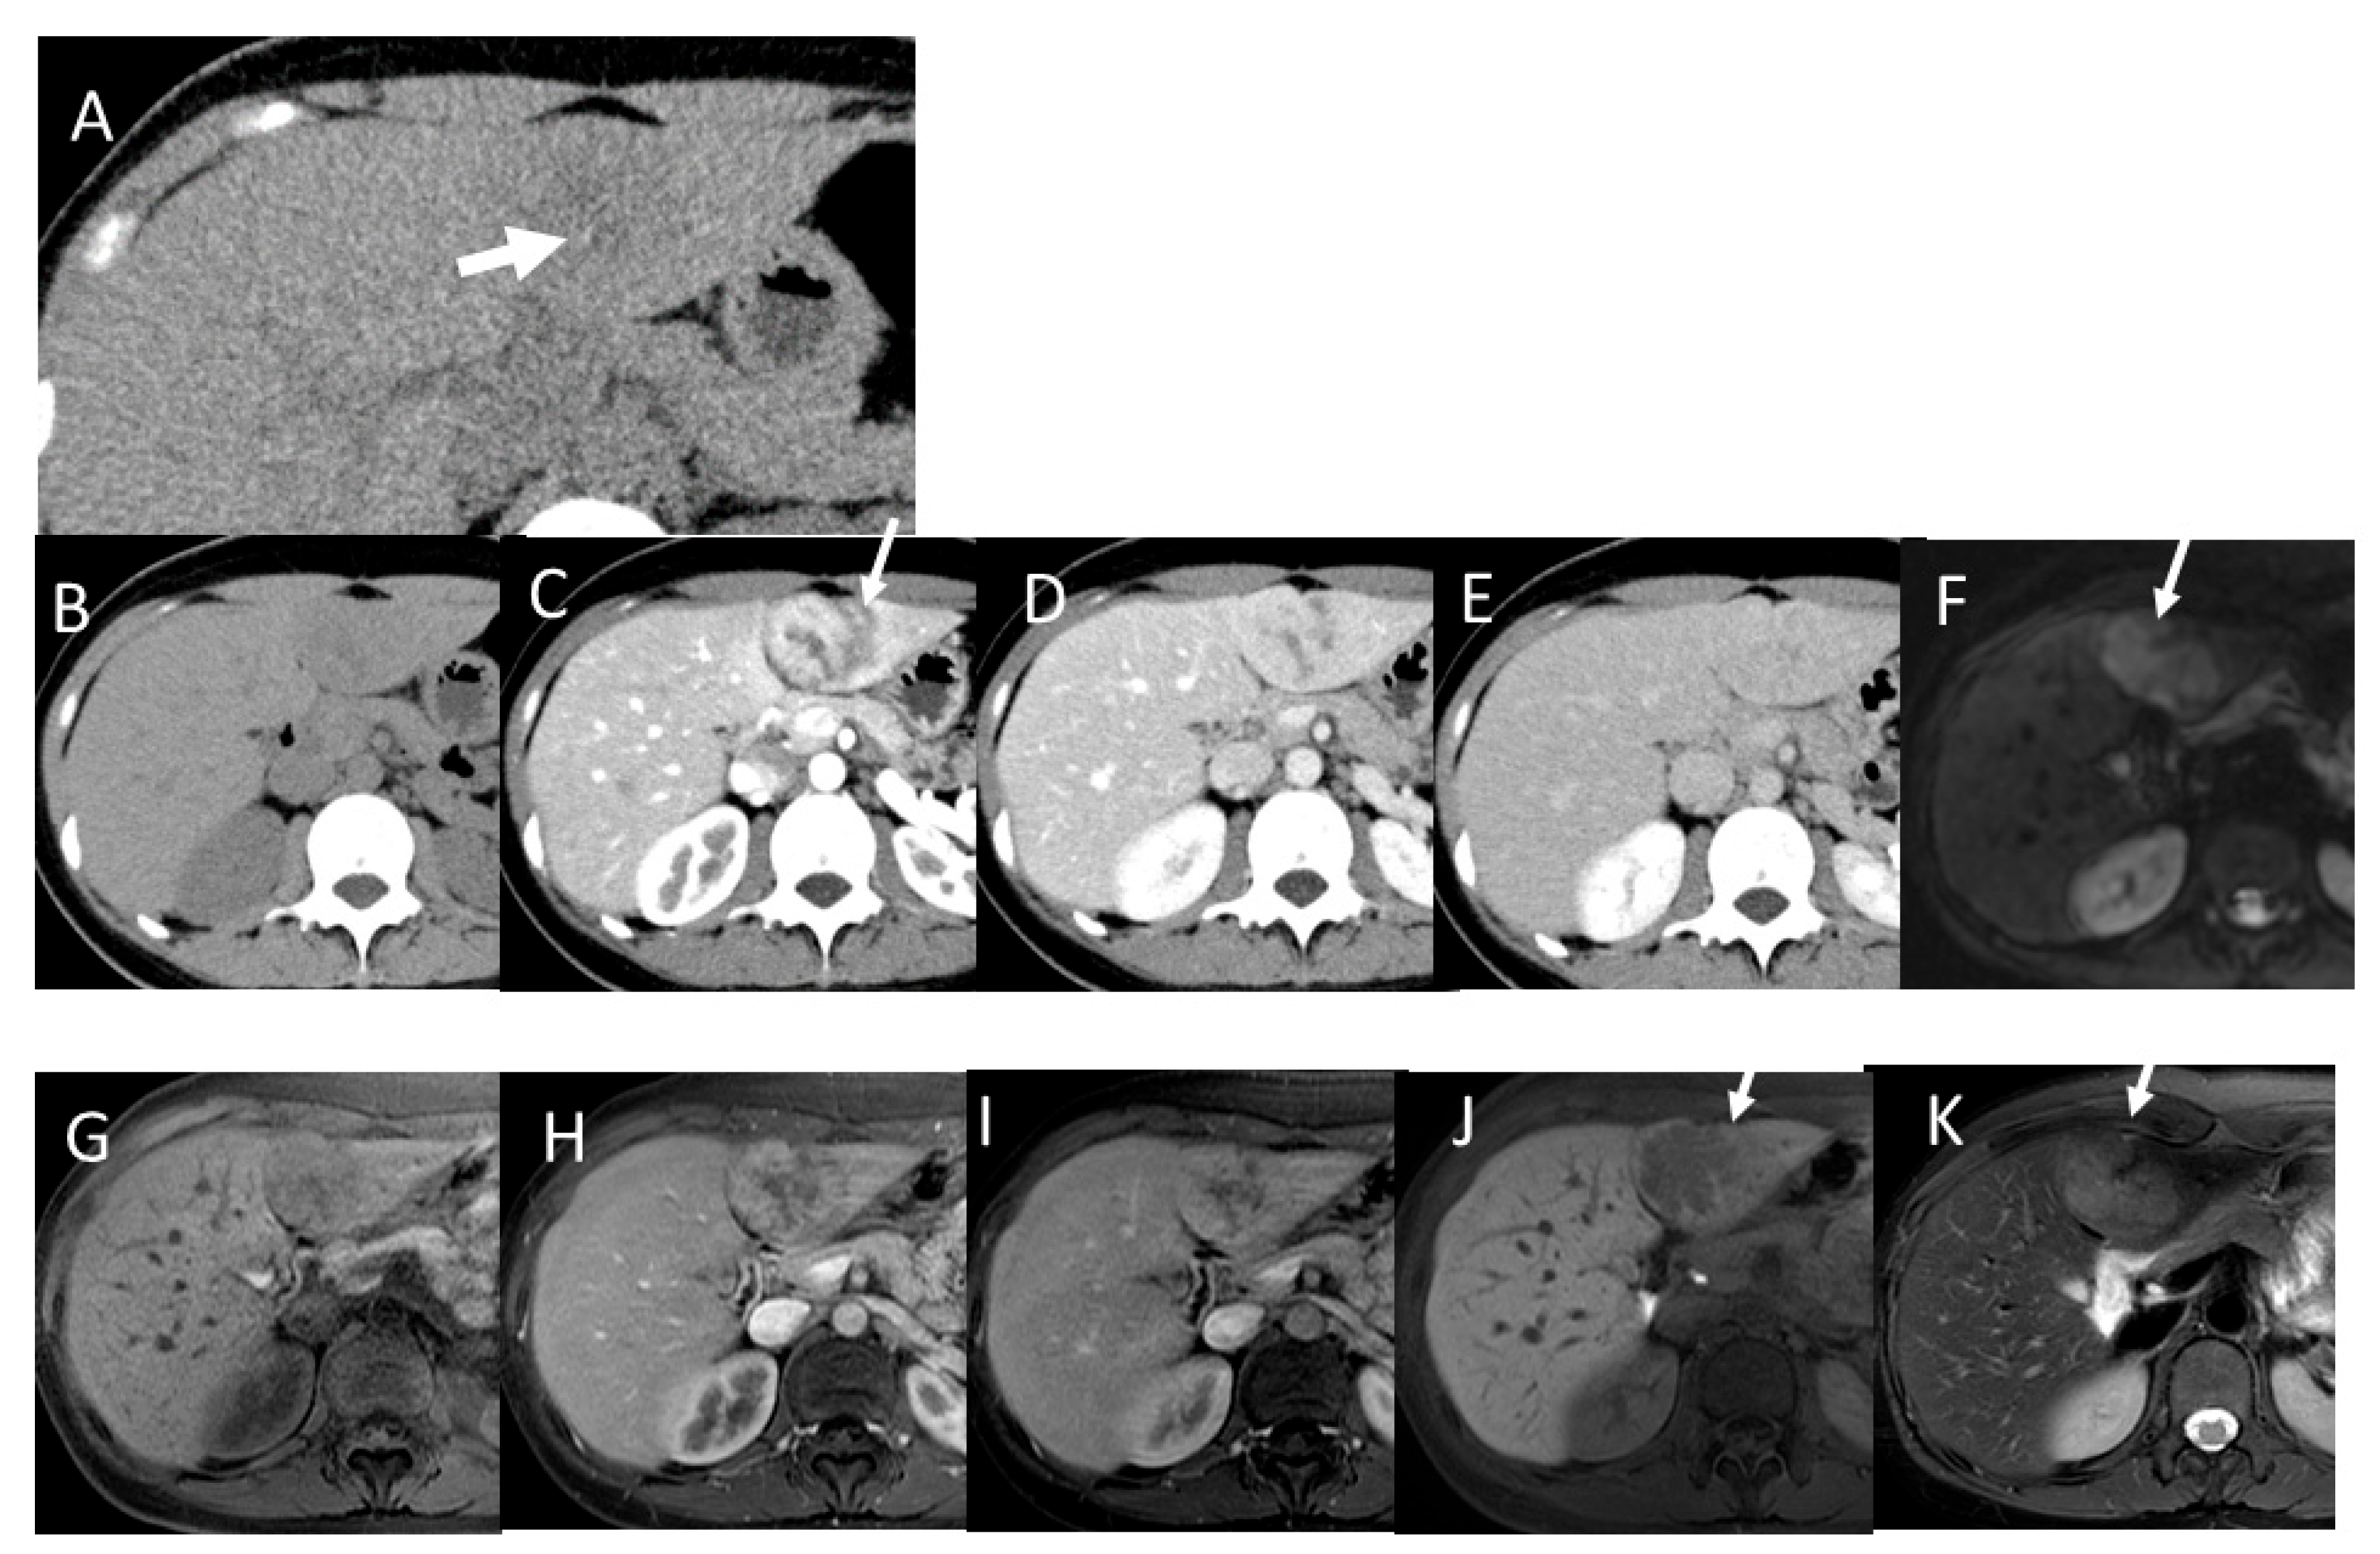

3.1. CT and MR Features of Liver Cirrhosis (LC)

4.7. Combined Hepatocellular and Cholangiocarcinoma (cHCC-CCA)

4.8. Steatohepatitic HCC (SH-HCC)